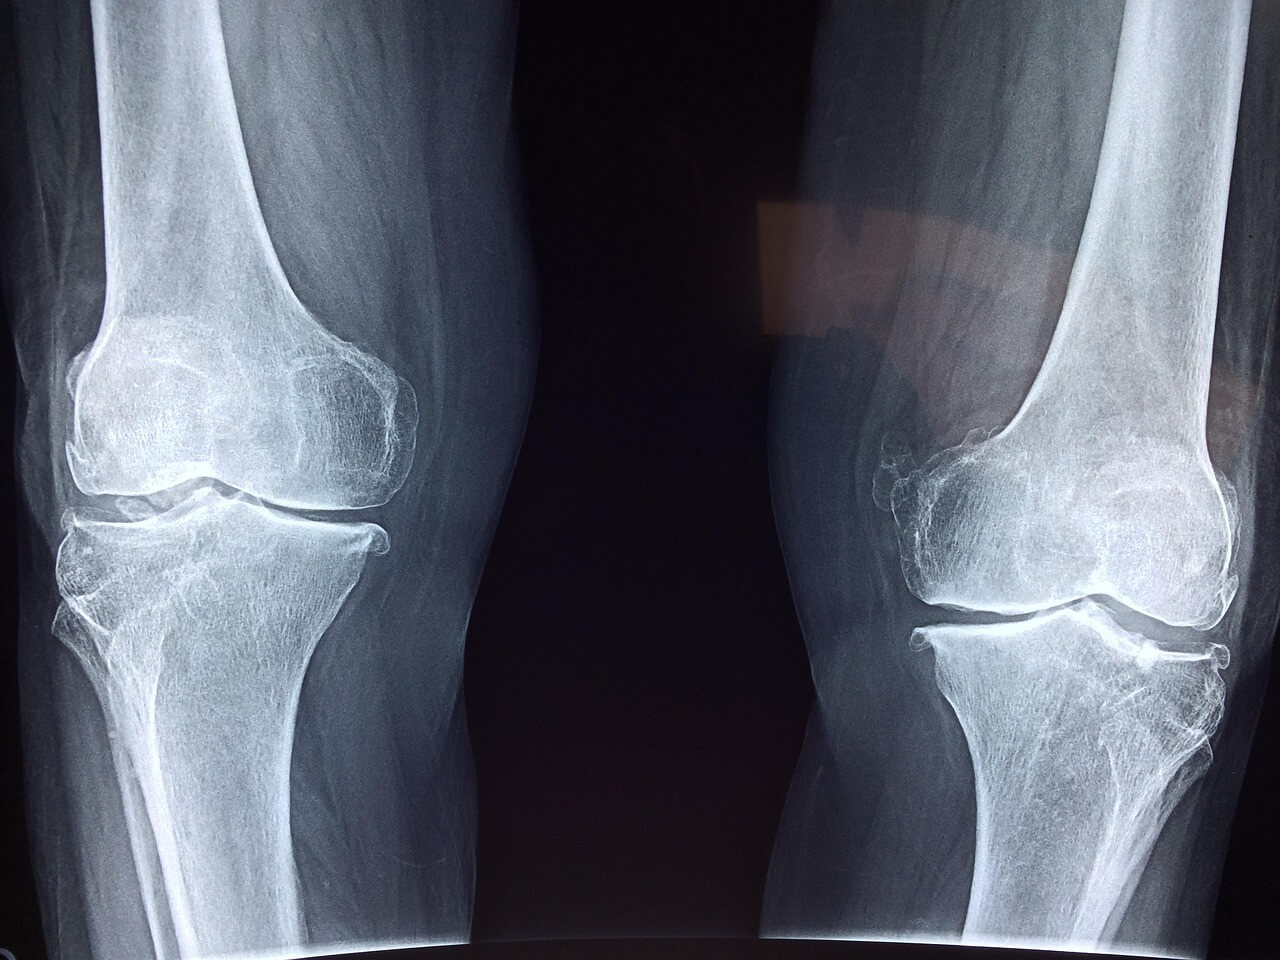

진단 방법

조기 진단을 위해 다음과 같은 검사가 필요합니다:

- X-ray: 뼈의 구조적 변형을 확인할 수 있으나 초기 단계에서는 잘 안 보일 수 있음.

- MRI: 가장 민감한 검사로 초기 골괴사를 정확히 확인 가능.

- CT 스캔: 병변의 위치와 범위를 더 정밀하게 분석 가능.

Q7. 골괴사는 어떤 검사로 확인하나요?

X-ray로 확인이 어려운 초기 골괴사는 MRI 검사가 가장 정확합니다. CT, 혈액검사도 보조적으로 시행됩니다.